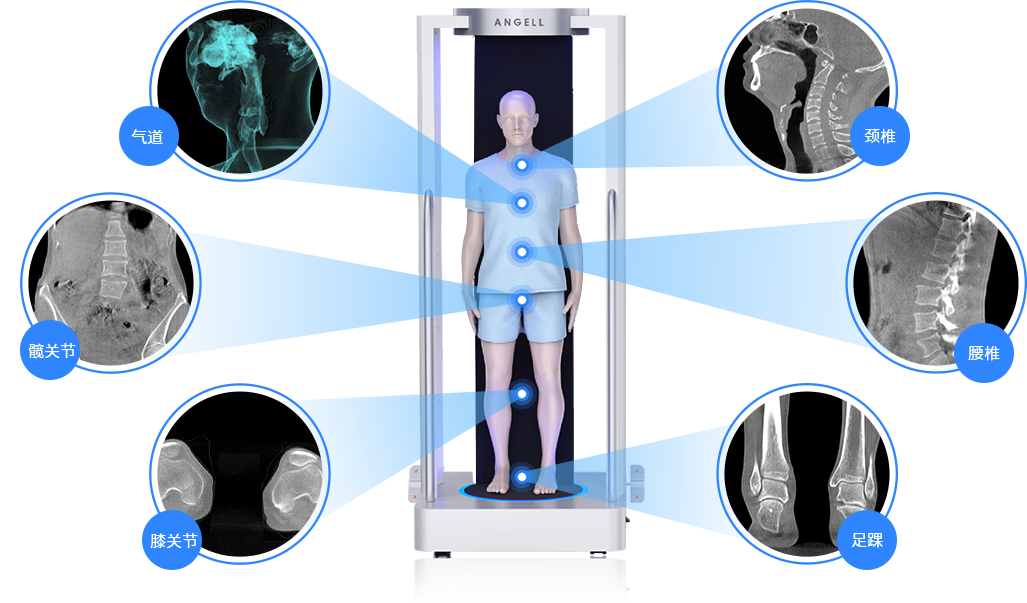

負重位動態(tài)多角度攝影功能

國內(nèi)首創(chuàng)真三維數(shù)字化X線攝影系統(tǒng)

· 補位CT,提供負重位三維影像

· 引領(lǐng)普放走向三維精準診斷時代

獨特的負重位三維影像

填補常規(guī)CT/MR空白

獨特的負重位三維影像

氣道

髖關(guān)節(jié)

膝關(guān)節(jié)

頸椎

腰椎

足踝